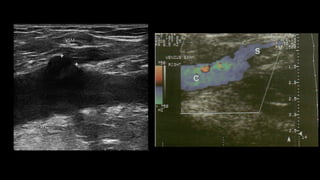

• Vena poplítea:

vSuperficial a la arteria poplítea.

vEje transversal: comprobar compresibilidad.

üPara demostrar la permeabilidad y competencia se realiza la

maniobra de compresión externa, tiene alta sensibilidad y

especificidad para detectar trombosis. De preferencia se realiza en un

corte transversal del vaso para evitar desplazamiento.

üPara demostrar competencia valvular se utiliza la maniobra de

Valsalva a través de inspiración profunda y sostenida, el flujo al

Doppler color debe de cesar